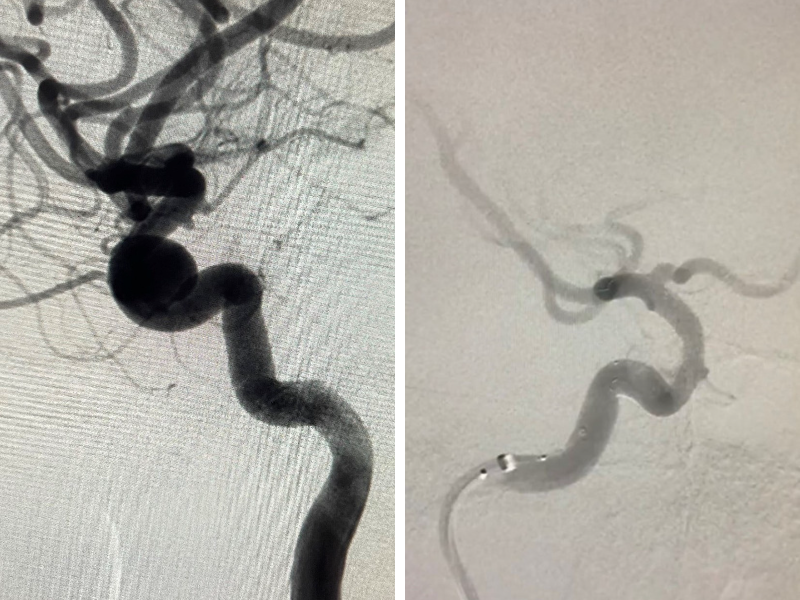

Hình 1. Hình ảnh thể hiện túi phình trước & sau khi can thiệp của người bệnh.

Tại BV Hoàn Mỹ Sài Gòn, người bệnh được thực hiện các xét nghiệm tiền phẫu, chuẩn bị và được can thiệp sớm ngay ngày hôm sau. Sau khi trao đổi kỹ với bệnh nhân và gia đình về tình trạng bệnh và phương pháp điều trị, các bác sĩ đã thực hiện điều trị bằng phương pháp đặt stent thay đổi dòng chảy. Đây là một phương pháp điều trị mới, hiện đại, hiệu quả nhất hiện nay cho các túi phình có kích thước lớn. Stent sẽ hướng dòng chảy theo chiều mạch máu và không đổ vào túi phình nữa, về lâu dài túi phình sẽ huyết khối, tổ chức hoá và teo nhỏ lại, cổ túi phình sẽ liền với mạch máu (quá trình này gọi là nội mạc hoá), từ đó sẽ loại bỏ hoàn toàn túi phình. Quá trình can thiệp diễn ra thuận lợi và thành công, sau khi theo dõi thêm 1 ngày, tình trạng cô G. đã ổn định, hết đau đầu, có thể ngồi dậy, đi lại nhẹ nhàng, có thể tự mình thực hiện các chăm sóc cá nhân, không phụ thuộc vào người thân như lúc trước và được xuất viện ngay sau đó trong sự hạnh phúc của bệnh nhân, gia đình và các y bác sĩ.